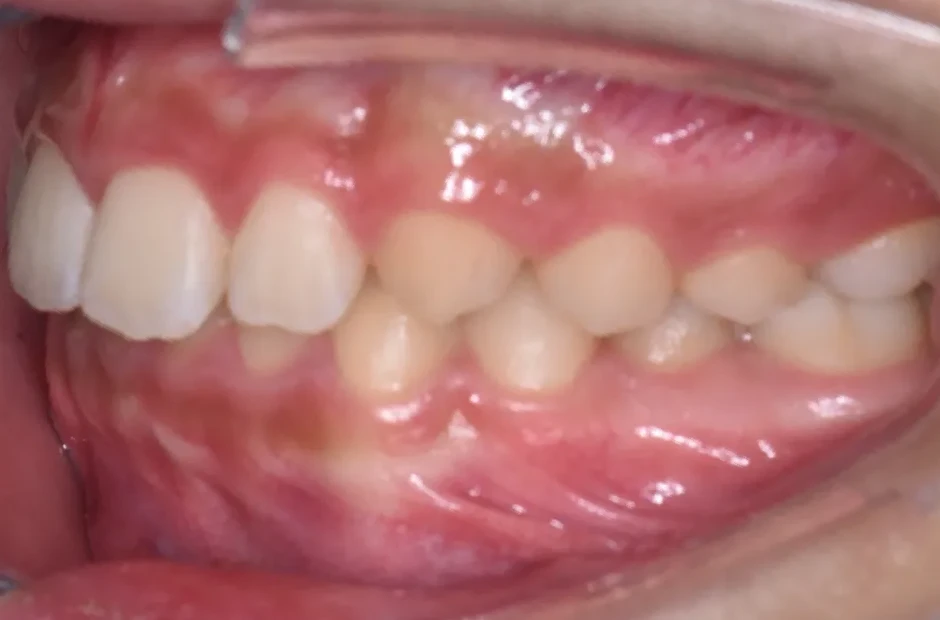

前歯部反対咬合

| 診断名・主訴 | 前歯部反対咬合 |

|---|---|

| 年齢・性別 | 14歳・男性 |

| 治療期間・回数 | 1年2か月 |

| 治療に用いた主な装置 | ブラケット矯正 |

| 抜歯部位 | なし |

| 治療費 | 60万円(税抜) |

| リスク・副作用 | 装置による違和感・疼痛・歯肉退縮・歯根吸収・虫歯のリスクなど |

治療前

治療後